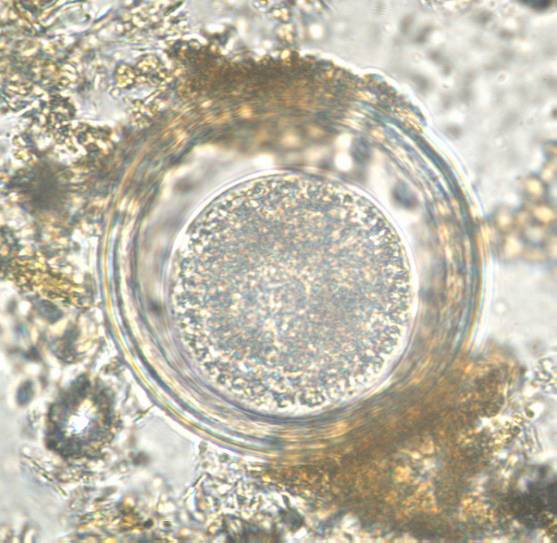

Coproscopy

All

Nematodes

Protozoa

Trematodes

Cestodes